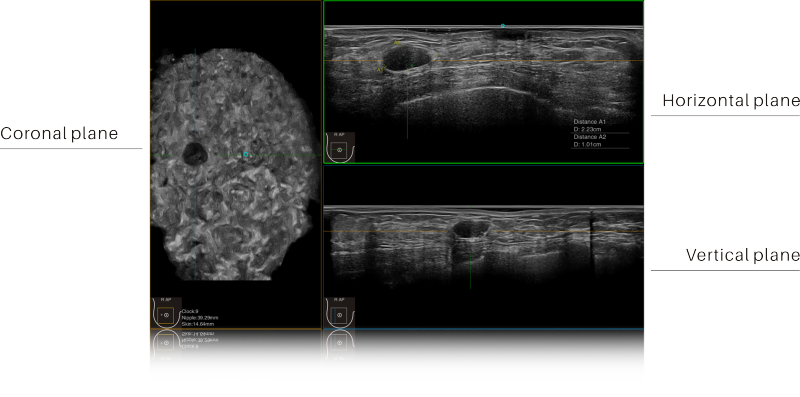

Full Volume Imaging and Coronal Section with High Clinical Value

IBUS acquires volume data from multiple sections to provide abundant information. The coronal section intuitively shows the anatomical information of breast tissue in a supine position during operation, which helps surgeon to perform more accurate surgical planning.

Intelligent Breast Solutions on the Workstation

Automatic lesion detection powered by AI identifies suspected area and traces the lesion from multiple sections. Quantitative coordinate position and graphic indication will be displayed for precise lesion localization.

Lesion stereo images are generated from volume data rendering. It provides intuitive and detailed information for better observation and lesion localization.

Lesion correlation correlates the information obtained from different scanning positions and sections to avoid misdiagnosis.